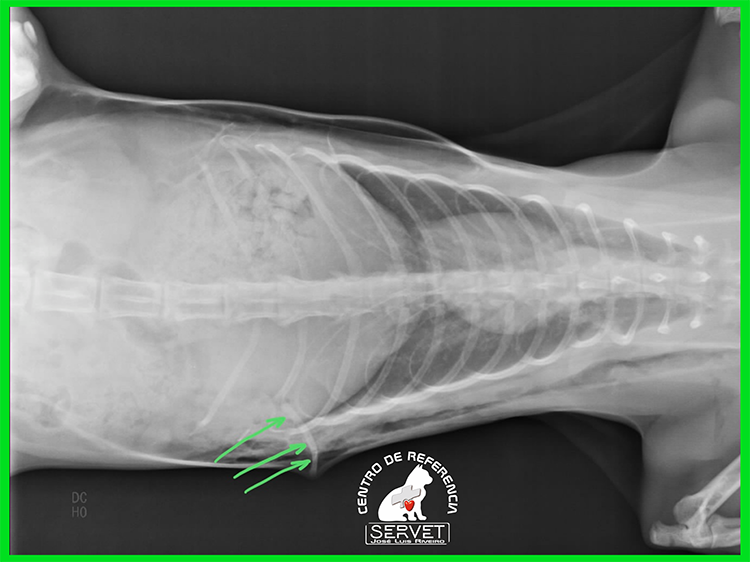

Enfisema subcutáneo

Una discontinuidad en la pared costal, asociada a una fractura costal (flechas verdes) producía un escape de aire desde el pulmón lesionado hacia el subcutáneo.